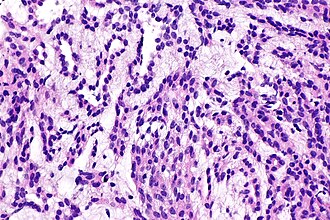

Renal mucinous tubular and spindle cell carcinoma. H&E stain. | |

| LM | mucin (foamy macrophages) - may be scant, spindle cells, small tubules - lined by cuboidal epithelium |

Microscopic

Features:[5]

- Mucin - may be scant.

- Often within foamy macrophages.

- Spindle cells - key feature.

- Often seen only focally.

- Small tubules - lined by cuboidal epithelium.[4]

The tumour consists of small cells with mild pleomorphism and mild-to-moderate cytoplasm. A tubular architecture is predominant and mucin is present. Focal spindled areas are also seen.